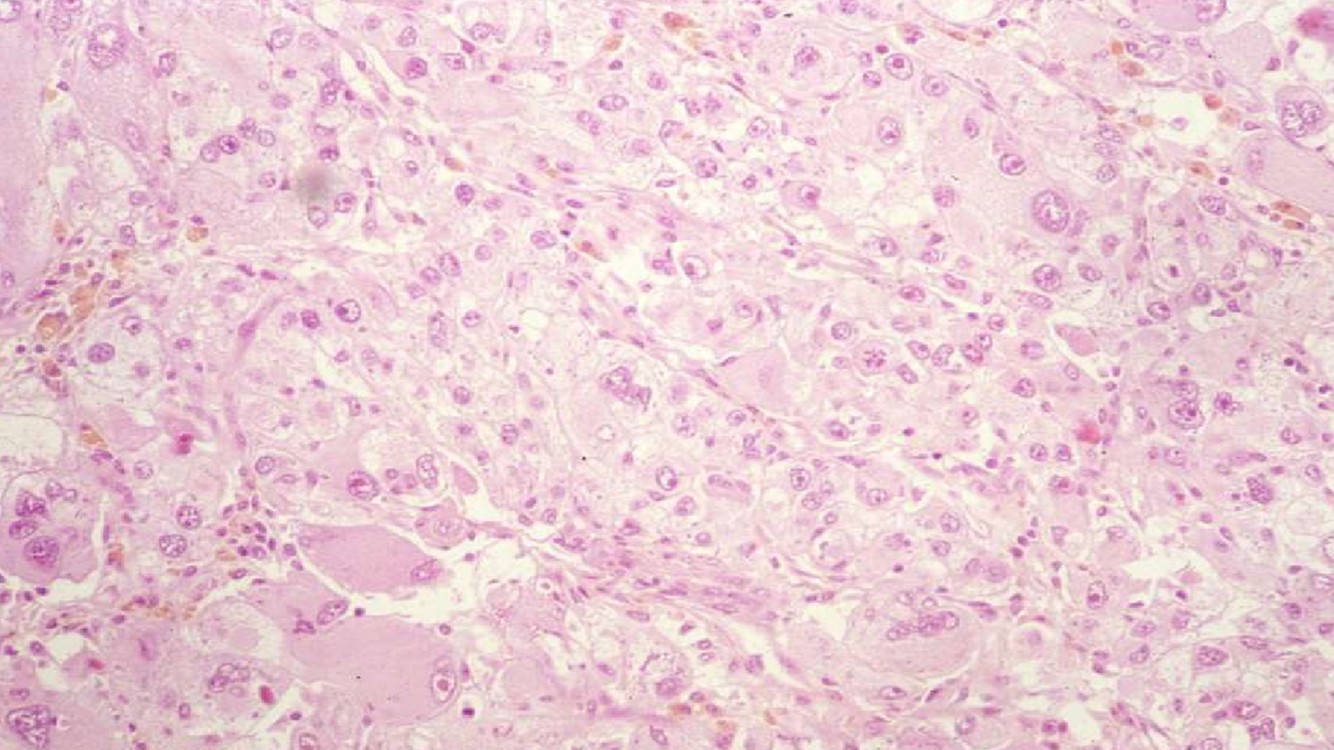

MEDULLARY CARCINOMA

- Medulla

- Typically young black man with sickle cell trait

- High-grade undifferentiated carcinoma

- INI1 negative

- Dismal prognosis